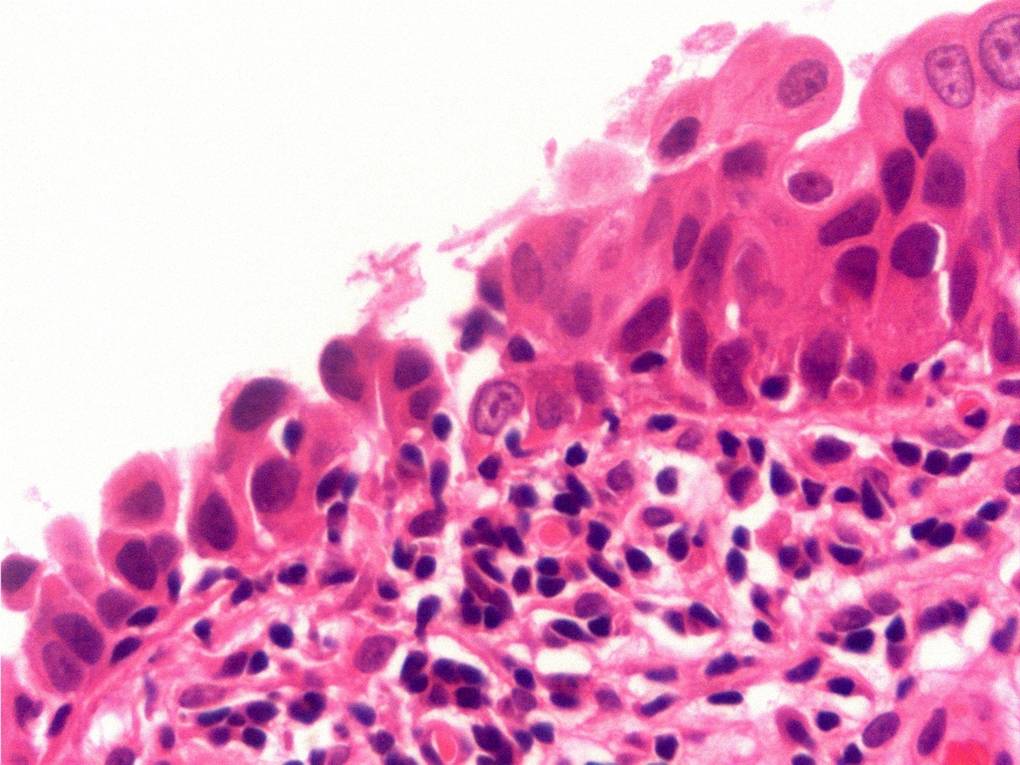

Bladder Flat Lesions

Case ID: 88